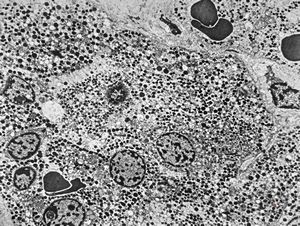

M, 23y. | acidophilic pituitary adenoma (STH)